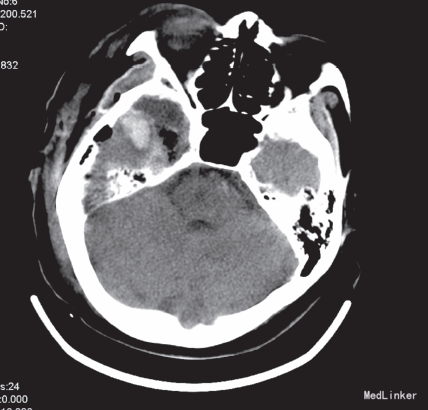

给予脱水、阿司匹林抗血小板治疗3天后病情无改善。再行头部增强MRI示:1、右侧颞叶及邻近的丘脑区可见一长增强后明显强化,高级别胶质瘤可能大;2、双侧半卵圆中心内多发缺血梗塞灶。在全麻下行开颅手术,术中见:右侧基底节区见异常脑组织,色黄,质韧,血供不丰富,与周围脑组织分界不清,前颅底见一包块大小约1.5cm×2cm ×2cm,色红,血供丰富,余无特殊。行“开颅右侧基底节区、第三脑室及前颅底占位切除术+颅内减压术+颅内压探头置入术”,术后病检示:间变型少突-星形细胞瘤(WHO,Ⅲ级)。术后给予脱水降压及营养神经治疗,复查头部CT示:右侧颞叶术区见积液、积气影,局部见出血灶,血肿大小约2.2×1.4cm,周围少许脑组织水肿。术后三天患者神智逐渐恢复,反应仍迟钝,左上肢肌力恢复至2 级,下肢肌力仍为2+级。10天后患者出现少量咳嗽咯痰,痰不易咯出,查体体温正常,双肺均闻及少许湿罗音,复查血常规示白细胞计数14.30×109/L,中性分叶核粒细胞百分率85.3%,(未行影像学检查),考虑肺部感染,给予他唑仙抗感染,治疗1 天后咳嗽咳痰无明显好转。2天后患者突发意识障碍,呈深昏迷,叹气样呼吸,血压及氧饱和度测不出,双侧瞳孔散大固定,直径0.6cm,对光反射消失,经积极抢救无效死亡。